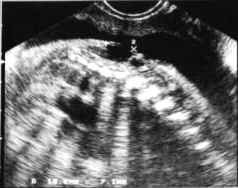

- Coupes transversales :

Ouverture des lames postérieures +/- marquées : Aspects classiquement décrits en U, en V ou en cupule (spina plan) selon le redressement ou la pergence des lames postérieures.

cliché gauche

Visibilité des cloisons dans la hernie méningée confirmant le diagnostic de myélo-méningocèle.